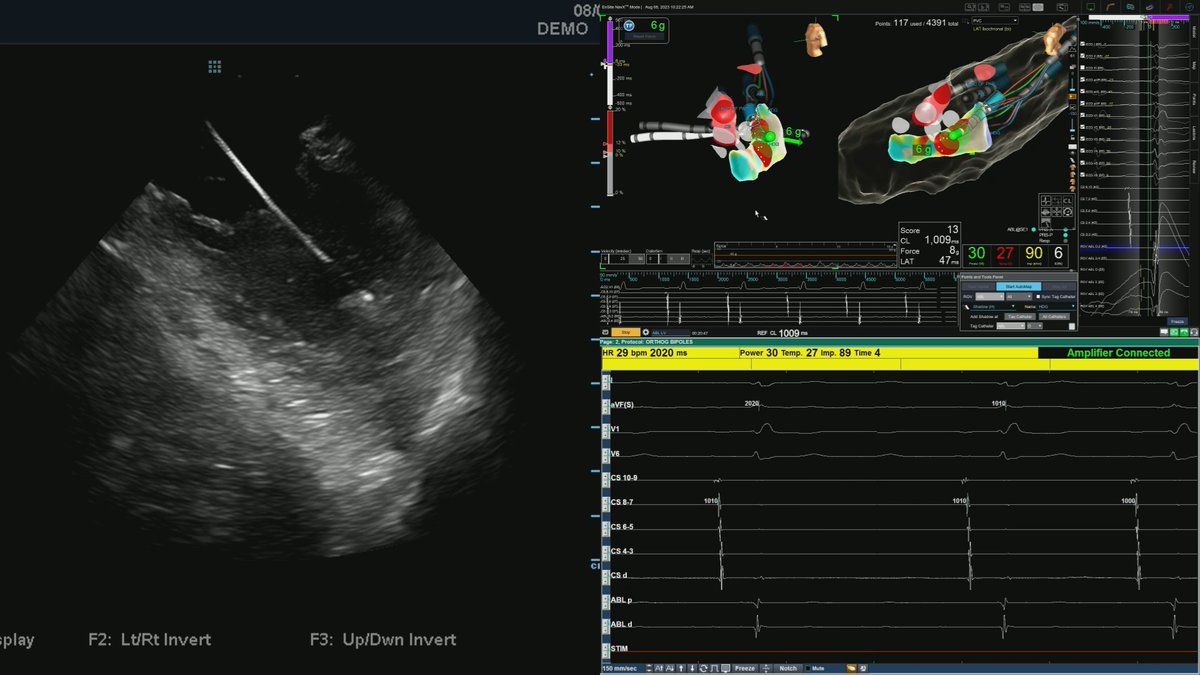

Volt released some pretty impressive 12 month data with over 80% success in paroxysmals and excellent persistent AF results. Read the simultaneous publication! kwnsfk27.r.eu-west-1.awstrack.me/L0/https:%2F%2…